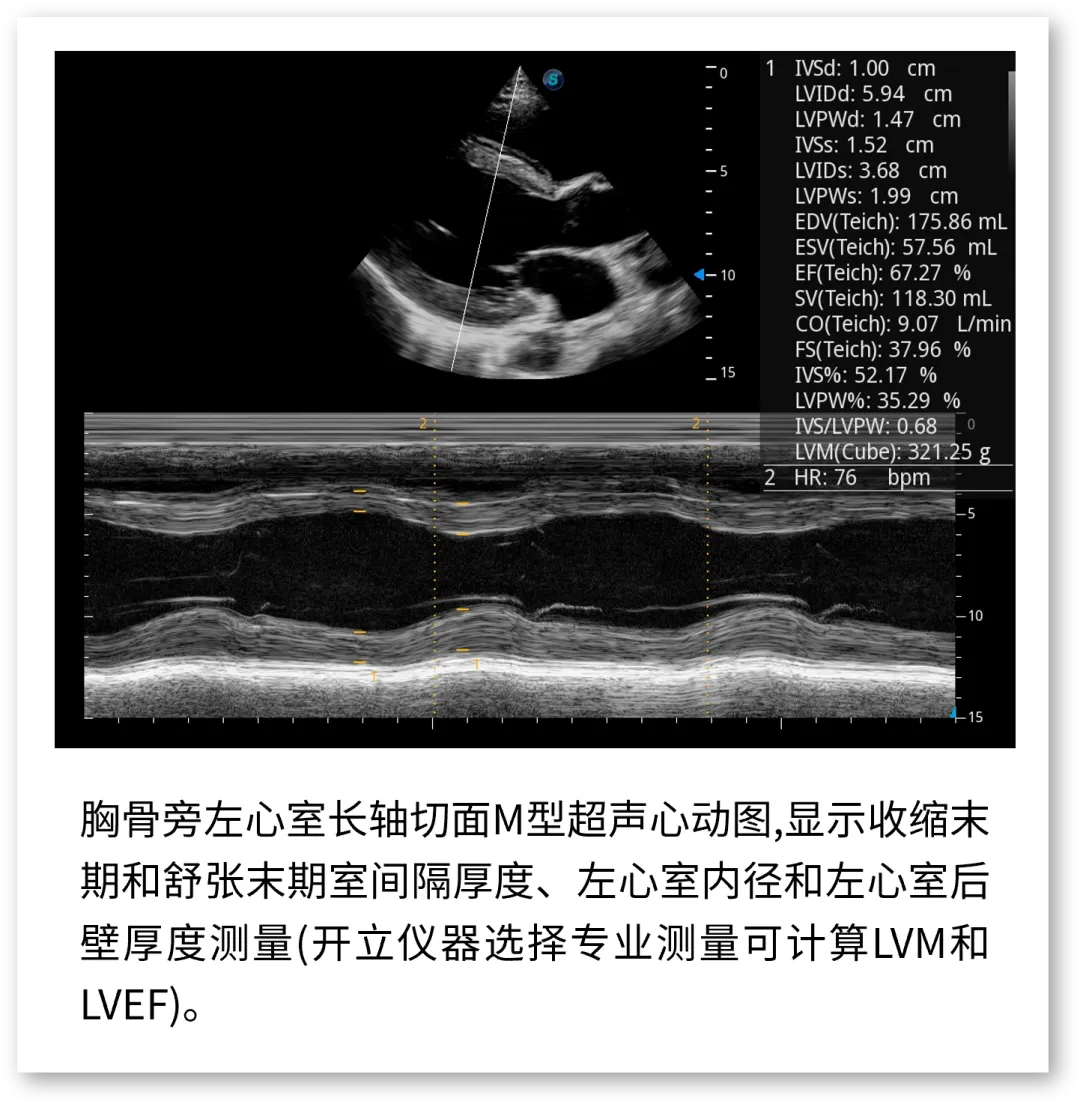

开立医疗联合武汉大学中南医院心血管病医院,将《心脏超声检查规范化中国专家共识 (2024版)》内容与实际临床工作需求融合,精心制作了指南挂图,助力标准采集,规范测量,期待这份实用且高清的工具,能成科室提升超声质效的助手!